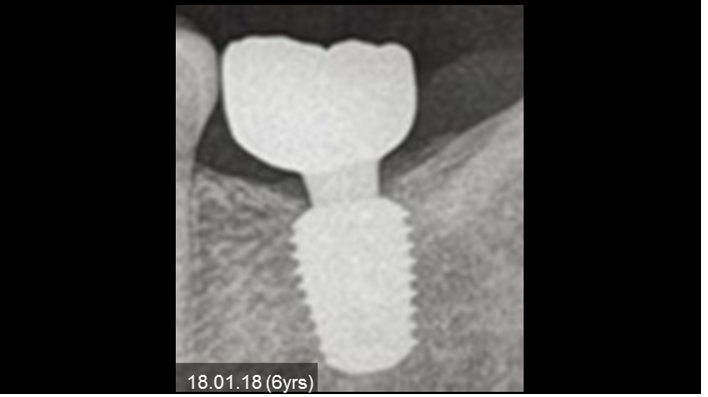

Clinical case: Bone growth in deepest thread of 8.0mm AnyRidge fixture

- Courtesy of Dr. Kwang Bum Park -

Clinical case: Bone filling into the bottom of deepest thread at 8.0mm AnyRidge fixture

Keywords

AnyRidge, Knifethread ,extraction socket, ,initial stability ,Allograft, ,osseointegratio ,Dr. Kwang Bum Park, , Mandibular, Single replacement, AnyRidge, Mega-oss,

Products used

Implant system-AnyRidge, Regeneration-Mega-Oss